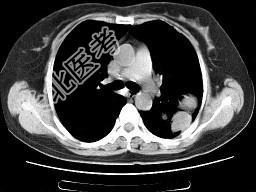

- 单项选择题女,52岁, 左侧背痛一月,胸部CT如图, 最可能的诊断为 ( )

A、左肺中央型肺癌

B、左肺周围型肺癌

C、左肺感染

D、左肺炎性假瘤

E、肺隔离征